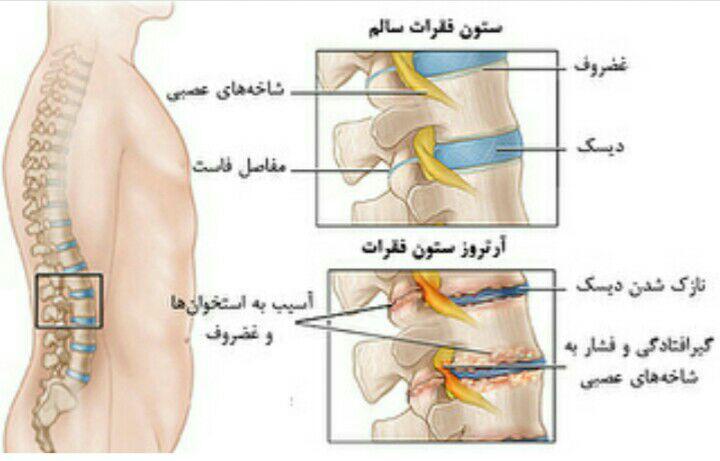

-درمان آرتروز مفاصل

-PRP و اوزون تراپی آرتروز مفصلی

دردهای اسکلتی عضلانی (کمردرد، گردندرد، زانودرد، آرتروز)